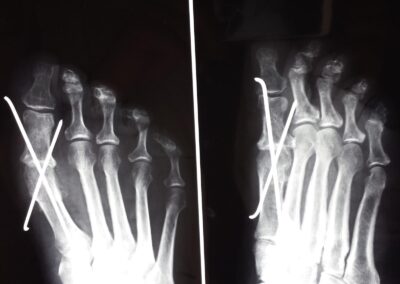

Le tecniche chirurgiche a nostra disposizione sono molteplici e vanno individualizzate sul paziente. Tra le varie preferisco la osteotomia distale del primo metatarso fissata con adeguati mezzi di sintesi preferibilmente in titanio associata al rilascio della capsula sul versante laterale. In alcuni casi difficili può essere indicato associare anche una osteotomia della prima falange dell’alluce oltre a trattamenti diretti alla correzione di eventuali griffe digitali associate.

Il problema della chirurgia riparativa dell’ alluce valgo è la recidiva della deformità che addirittura è meno grave della ipercorrezione con conseguente alluce varo secondario. Occorre dunque programmare le osteotomie eventualmente associate alla testa del primo metatarso ed alla base della prima falange con un accurato planning preoperatorio in base a parametri morfologici da ricercare in una radiografia preoperatoria eseguita sotto carico gravitario.E’ fondamentale associare un riequilibrio delle parti molli capsulari e tendinee che andranno opportunemente adattate alla nuova configurazione geometrica dell’avampiede.Sarà poi importante l’ausilio di bendaggi o taping nelle prime settimane postoperatorie a mantenere la correzione ottenuta fino alla completa guarigione delle correzioni ossee e delle parti molli.Preciso che è fondamentale seguire l’evoluzione della cicatrizzazione con controlli ogni due settimane nei primi 45gg postoperatori con possibilità di correggere con adeguati taping eventuali iper piuttosto che ipo correzioni.